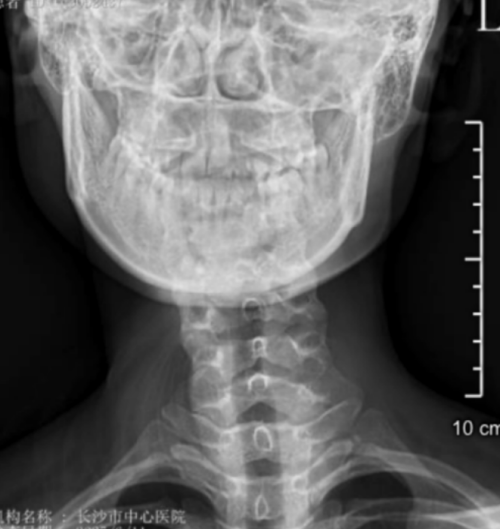

“患者属于典型的先天性肌性斜颈,由于延误治疗,颈部肌肉已形成纤维化改变。”该院脊柱外科二区主任、副主任医师曾浩介绍。面对这个特殊病例,医疗团队决定采用先进的微创技术——通过仅3厘米的切口,在放大数倍的手术视野下,精准松解挛缩的胸锁乳突肌,同时保护重要的神经血管。